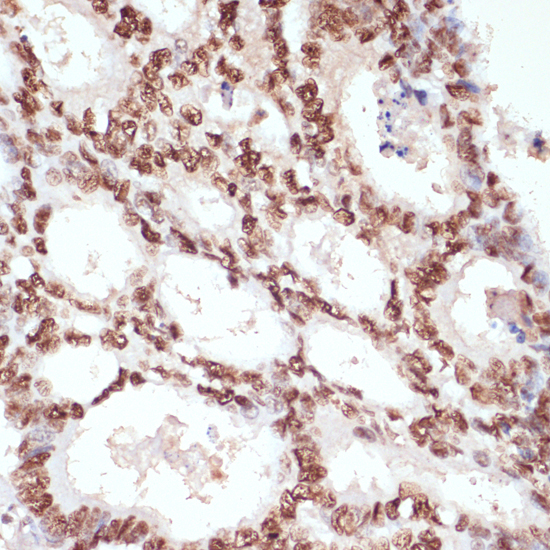

Immunohistochemistry of paraffin-embedded human skin using Phospho-beta Catenin-S33/S37/T41 antibody.